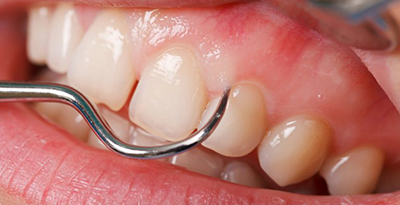

Фото 1. Стоматолог проверяет оголяются ли корни и шейка зубов у пациента, страдающего пародонтозом, при помощи зонда.